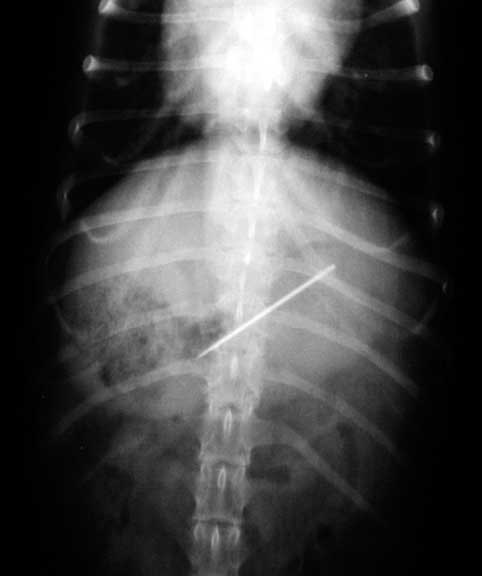

This ferret is lying on its back with the head at the top. It is called a VD (venture-dorsal) view

On the VD view the mildly opaque foreign body is at the beginning of the small intestines called the duodenum